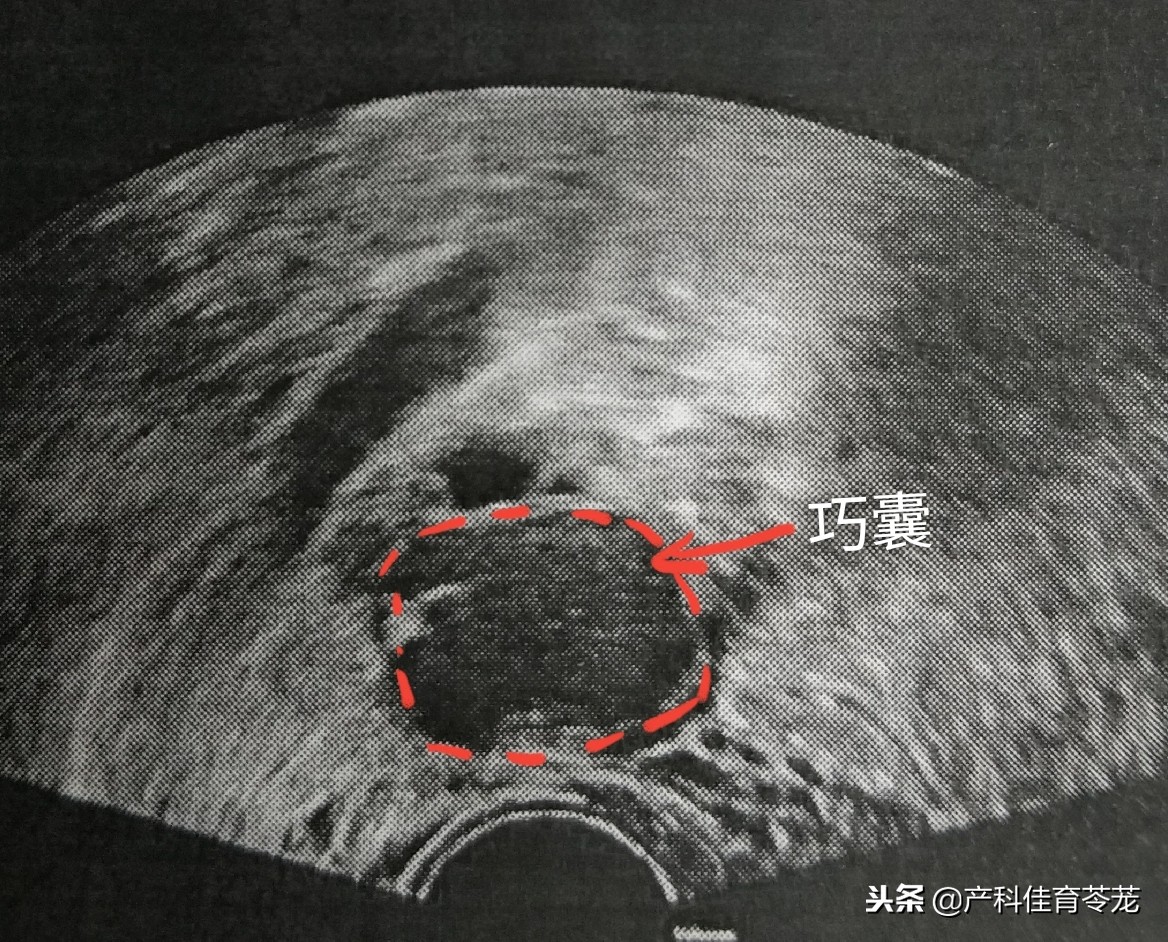

1、卵巢巧克力囊肿(内膜异位囊肿)

子宫内膜组织异位于卵巢,这些异位灶反复出血形成囊肿,里面是暗褐色粘糊状陈旧性血液,像巧克力,故又称为巧克力囊肿。

这种囊肿B超诊断准确率很高:

同样里面是液体,但B超下看到的不是透亮的,里面有密集的细点状回声,说明不是单纯的一包“水”,而是有血。